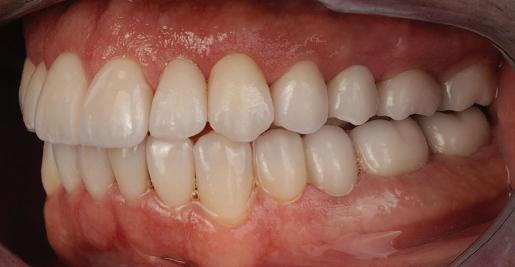

Пациентът постъпи в моята клини ка с наличие на темпоромандибуларен дисфункционален болков синдром, едно странно изместен диск с редукция в дяс ната става, клас II, подклас 2, тесни гор на и долна челюст със струпване, дъл бок овърбайт

орални снимки и снимки на позата, пал пация на мускулите, брукс-чекър, оклу зограми, кондилография, рентгеногра фии, СВСТ и ядрено-магнитен резонанс на темпоромандибуларните стави). Преди началото на ортодонтското лечение всички стари възстановява ния бяха свалени и бяха заменени с дъл госрочни временни от хибридна керами ка. На девитализираните зъби бе прове дено ендодонтско релечение. Индивиду ализиран оклузален сплинт бе направен с цел да се постигне контролирано репо зициониране на долната челюст, като носенето му продължи три месеца до възстановяване на правилната позиция на ставния диск и затихване на орофаци алната болка и дискомфорт в ставата. Брекетите в горната челюст бяха за лепени, за да започне подреждането и нивелирането на зъбите, докато паци ентът все още носеше сплинта. След края на терапията със сплинта бе на правена кондилография, за да се потвър ди триизмерната позиция на долната челюст. След залепване на брекетите в долна

тация на долната челюст. Дъга GUMMETAL с tip-back извивки бе поставена в долната челюст за ниве лиране кривата на Шпее. Случаят бе финализиран с 19x25 SS дъги в горната и долната зъбна дъга за координиране. Преди да се изготви финалният восъ чен моделаж, естетичните и лицеви те характеристики бяха анализирани с помощта на дигитален дизайн на ус мивката, за да се създаде мок-ъп, чии то форма и размери да бъдат одобрени от пациента. Бе оценена фонетиката и бяха заснети лицеви снимки и видеа. Зъ бите бяха изпилени, като препарация та бе изцяло водена от функционалния восъчен моделаж, прехвърлен в устата на пациента. След препарацията восъч ният моделаж бе напаснат и насложен върху препарационния модел и бе фрезо ван от e-max multi bl 1. Циментирането на финалните конструкции бе направе но при изолация с кофердам, следвайки адхезивния протокол. След циментирането бе направено проследяване на оклузията чрез снема не на отпечатъци, монтиране на моде лите в артикулатор в окончателната интеркуспидация и внимателно прове ряване за наличие на блокажи при воде ни движения.

В конкретния случай комбинирах златния стандарт при статична по зиция с динамична оценка на функци ята на темпоромандибуларната ста ва, за да диагностицирам и лекувам ней ната дисфункция.

Д-р Манол Ивчев, България, зт. Leandro Gambogi, Бразилия

6 Dental Tribune Bulgarian Edition / октомври 2022 г. КРАТКО ОПИСАНИЕ НА КЛИНИЧНИЯ СЛУЧАЙ

След стабилизира не на ставите и долната челюст в те рапевтична позиция постигнах орто донтски премествания и скелетни ко рекции, които обикновено са възмож ни единствено посредством ортогнат на хирургия. Преминах от аналогов мо дел на работа към изцяло дигитален, за да се хармонизира лицевата естетика чрез Digital Smile Design, като същевре менно обаче изработих функционален аналогов восъчен моделаж и на двете че люсти, за да мога да приложа оклузална та концепция на Славичек. След което напаснах препарациите с аналоговия во съчен моделаж при изцяло дигитални ус ловия с цел фрезоване на короните. Всич ки тези комбинации правят случая из ключително комплексен. В крайна сметка този сложен случай бе лекуван с най-добрата възможна ком бинация от възможности, които ана логовият и дигиталният свят предла гат, за да се постигне красота, която е следствие от отлична функция. ОКЛУЗАЛЕН „БАЛЕТ“ С РОЗОВАТА ЕСТЕТИКА Клиничен случай, победител в категория „Комплексно естетично възстановяване“ в конкурса „Усмивка на годината 2022“ Преди След